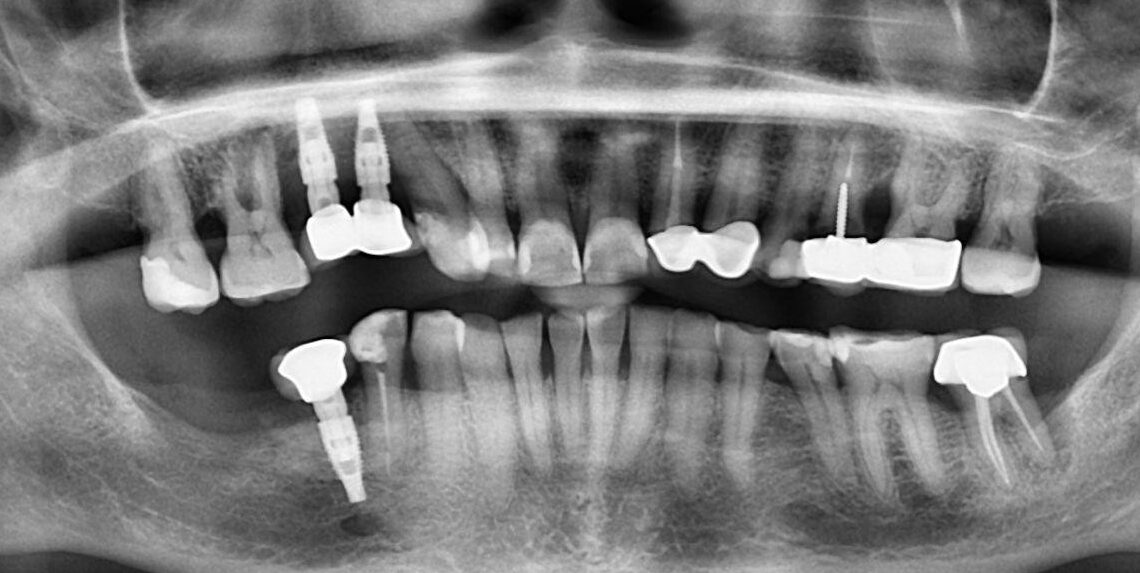

1.  What option cannot be selected for this panoramic X ray?

2. What option cannot be selected for upper jaw of this panoramic X ray?

3. What option cannot be selected for lower jaw of this panoramic X ray?